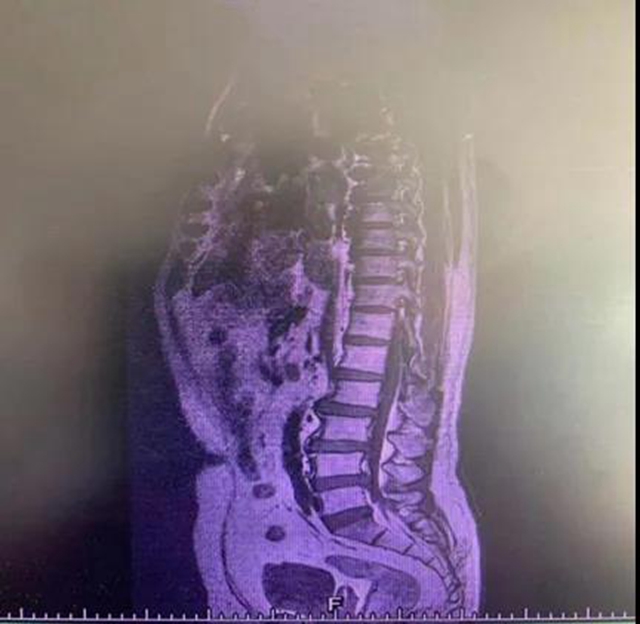

刘庆教授仔细查看了温先生相关检查结果,发现纤维环破裂神经根受压明显,与科室胡昕副教授和廖瑶主治医师等医生会诊后,决定予以“椎间孔镜手术”。

5月13日,胡昕副教授、廖瑶主治医师为温先生实施了“椎间孔镜手术”。手术很顺利,92分钟后,胡昕副教授从温先生腰椎取出21颗破碎的髓核。